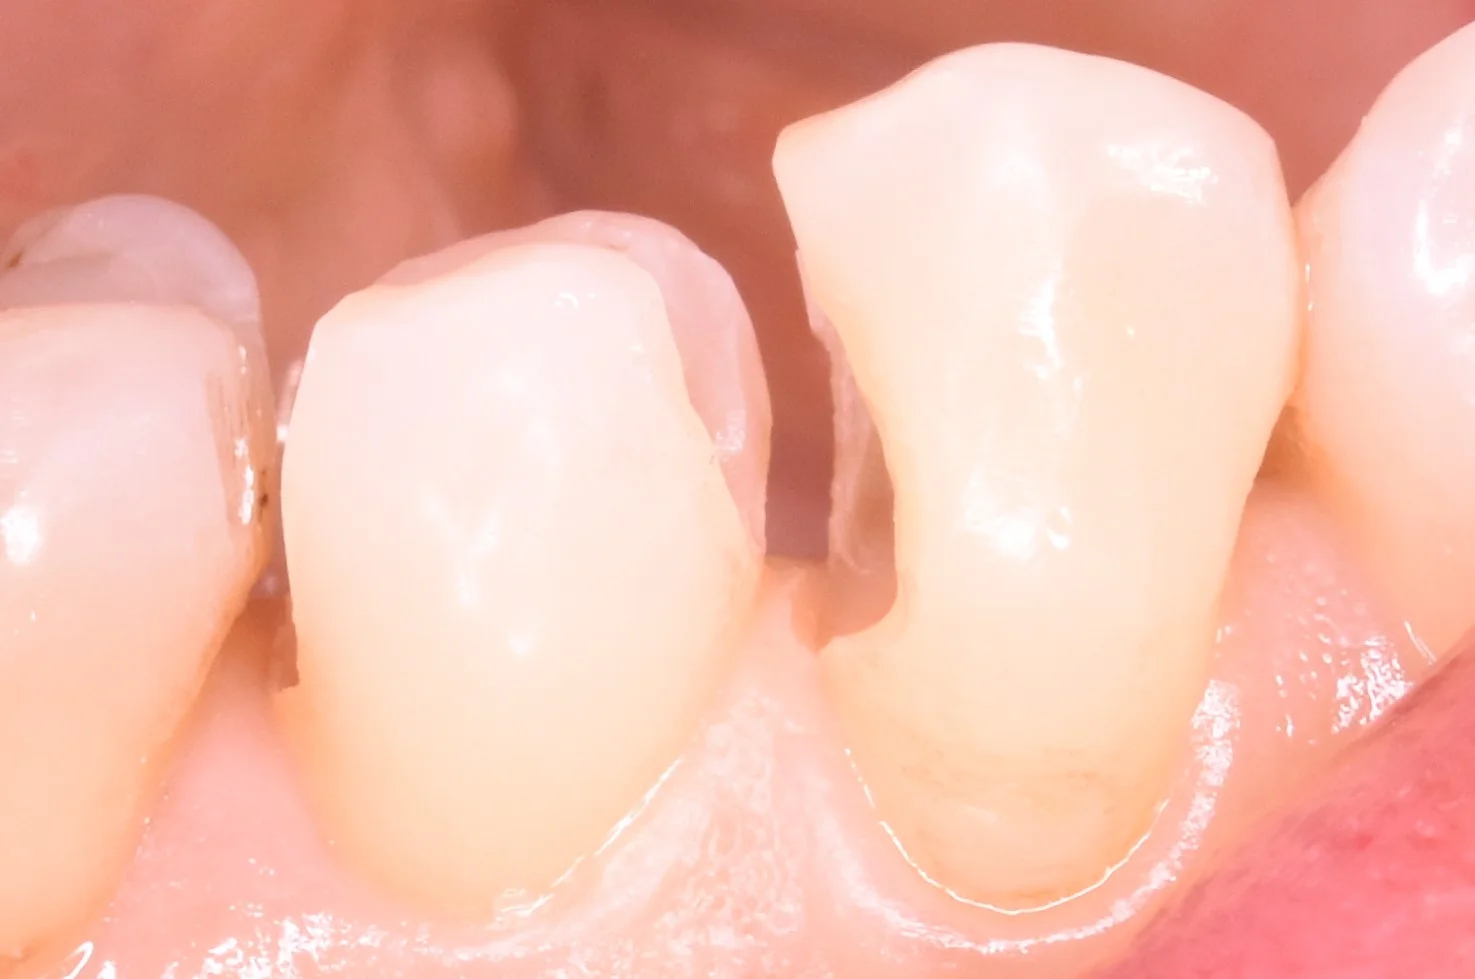

側面から見たのがこちらになります。

奥歯の歯並びが悪くなってしまっている所の治療|坂寄歯科医院(取手市藤代) - 画像6

側面から見ても、歯と歯の間の当たりは弱くなっていないのが分かるかと思います。

(若干出血していたので、それが歯の間に毛細管現象で入り込んでますね(-_-;))